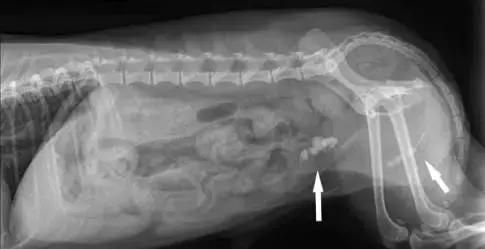

Lucky是一只3岁龄的贵宾,由于尿血到医院就诊。兽医师检查发现,TA的膀胱和尿道内有多颗结石。最后经过手术治疗,取出了大大小小数十颗石头。水中存在多种矿物质,其中钙镁含量较高的我们称为硬水。兽医学专家Chris Bessent 就发现,饮食中的镁离子对泌尿系统内的结晶体以及磷酸氨镁结石的形成有关。

lucky膀胱内和尿道内的结石